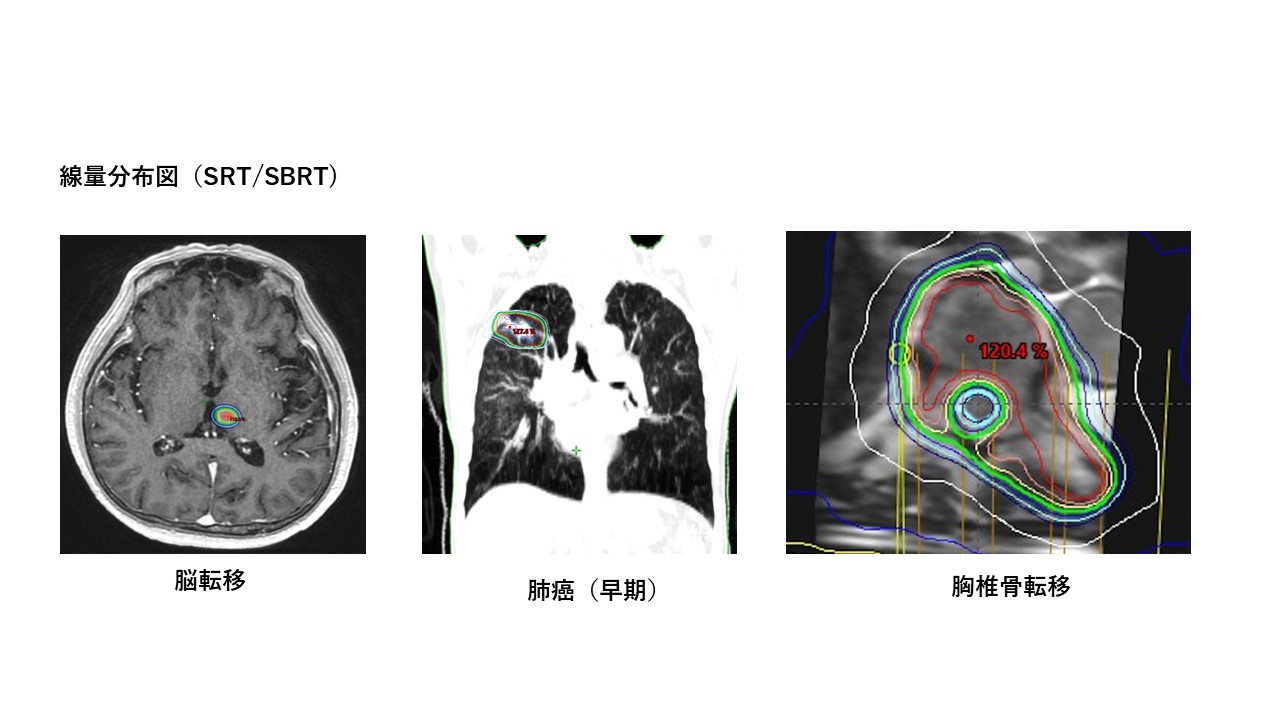

3. 定位放射線治療(Stereotactic radiotherapy: SRT)

比較的小さながん病巣に対し、周囲の正常臓器を避けて高線量の放射線を集中的にピンポイントで照射する治療です。ミリ単位の正確さでがん病変への強力な照射を行います。少ない回数(短期間)で安全に効果的な高線量を投与できます。

脳転移や、早期の肺癌や肝細胞癌などの体幹部の病巣に対して適用します(体幹部定位放射線治療:Stereotactic body radiotherapy: SBRT)。椎骨(背骨、腰骨)の骨転移には脊髄(神経)をくり抜くように避けての照射が可能です。